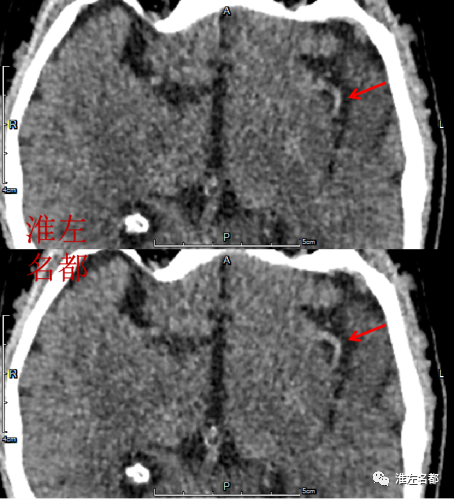

2020-12-14 18:35 复查CT

△颅脑CT平扫:左侧侧裂池和颞部蛛网膜下腔高密度范围缩小,CT密度值较前显著降低,提示之前高密度中混有碘造影剂。

△颅脑CT平扫:左侧颞叶前部低密度梗死,蛛网膜下腔高密度已经消失。

△颅脑CT平扫:所见同2020-12-16 CT。